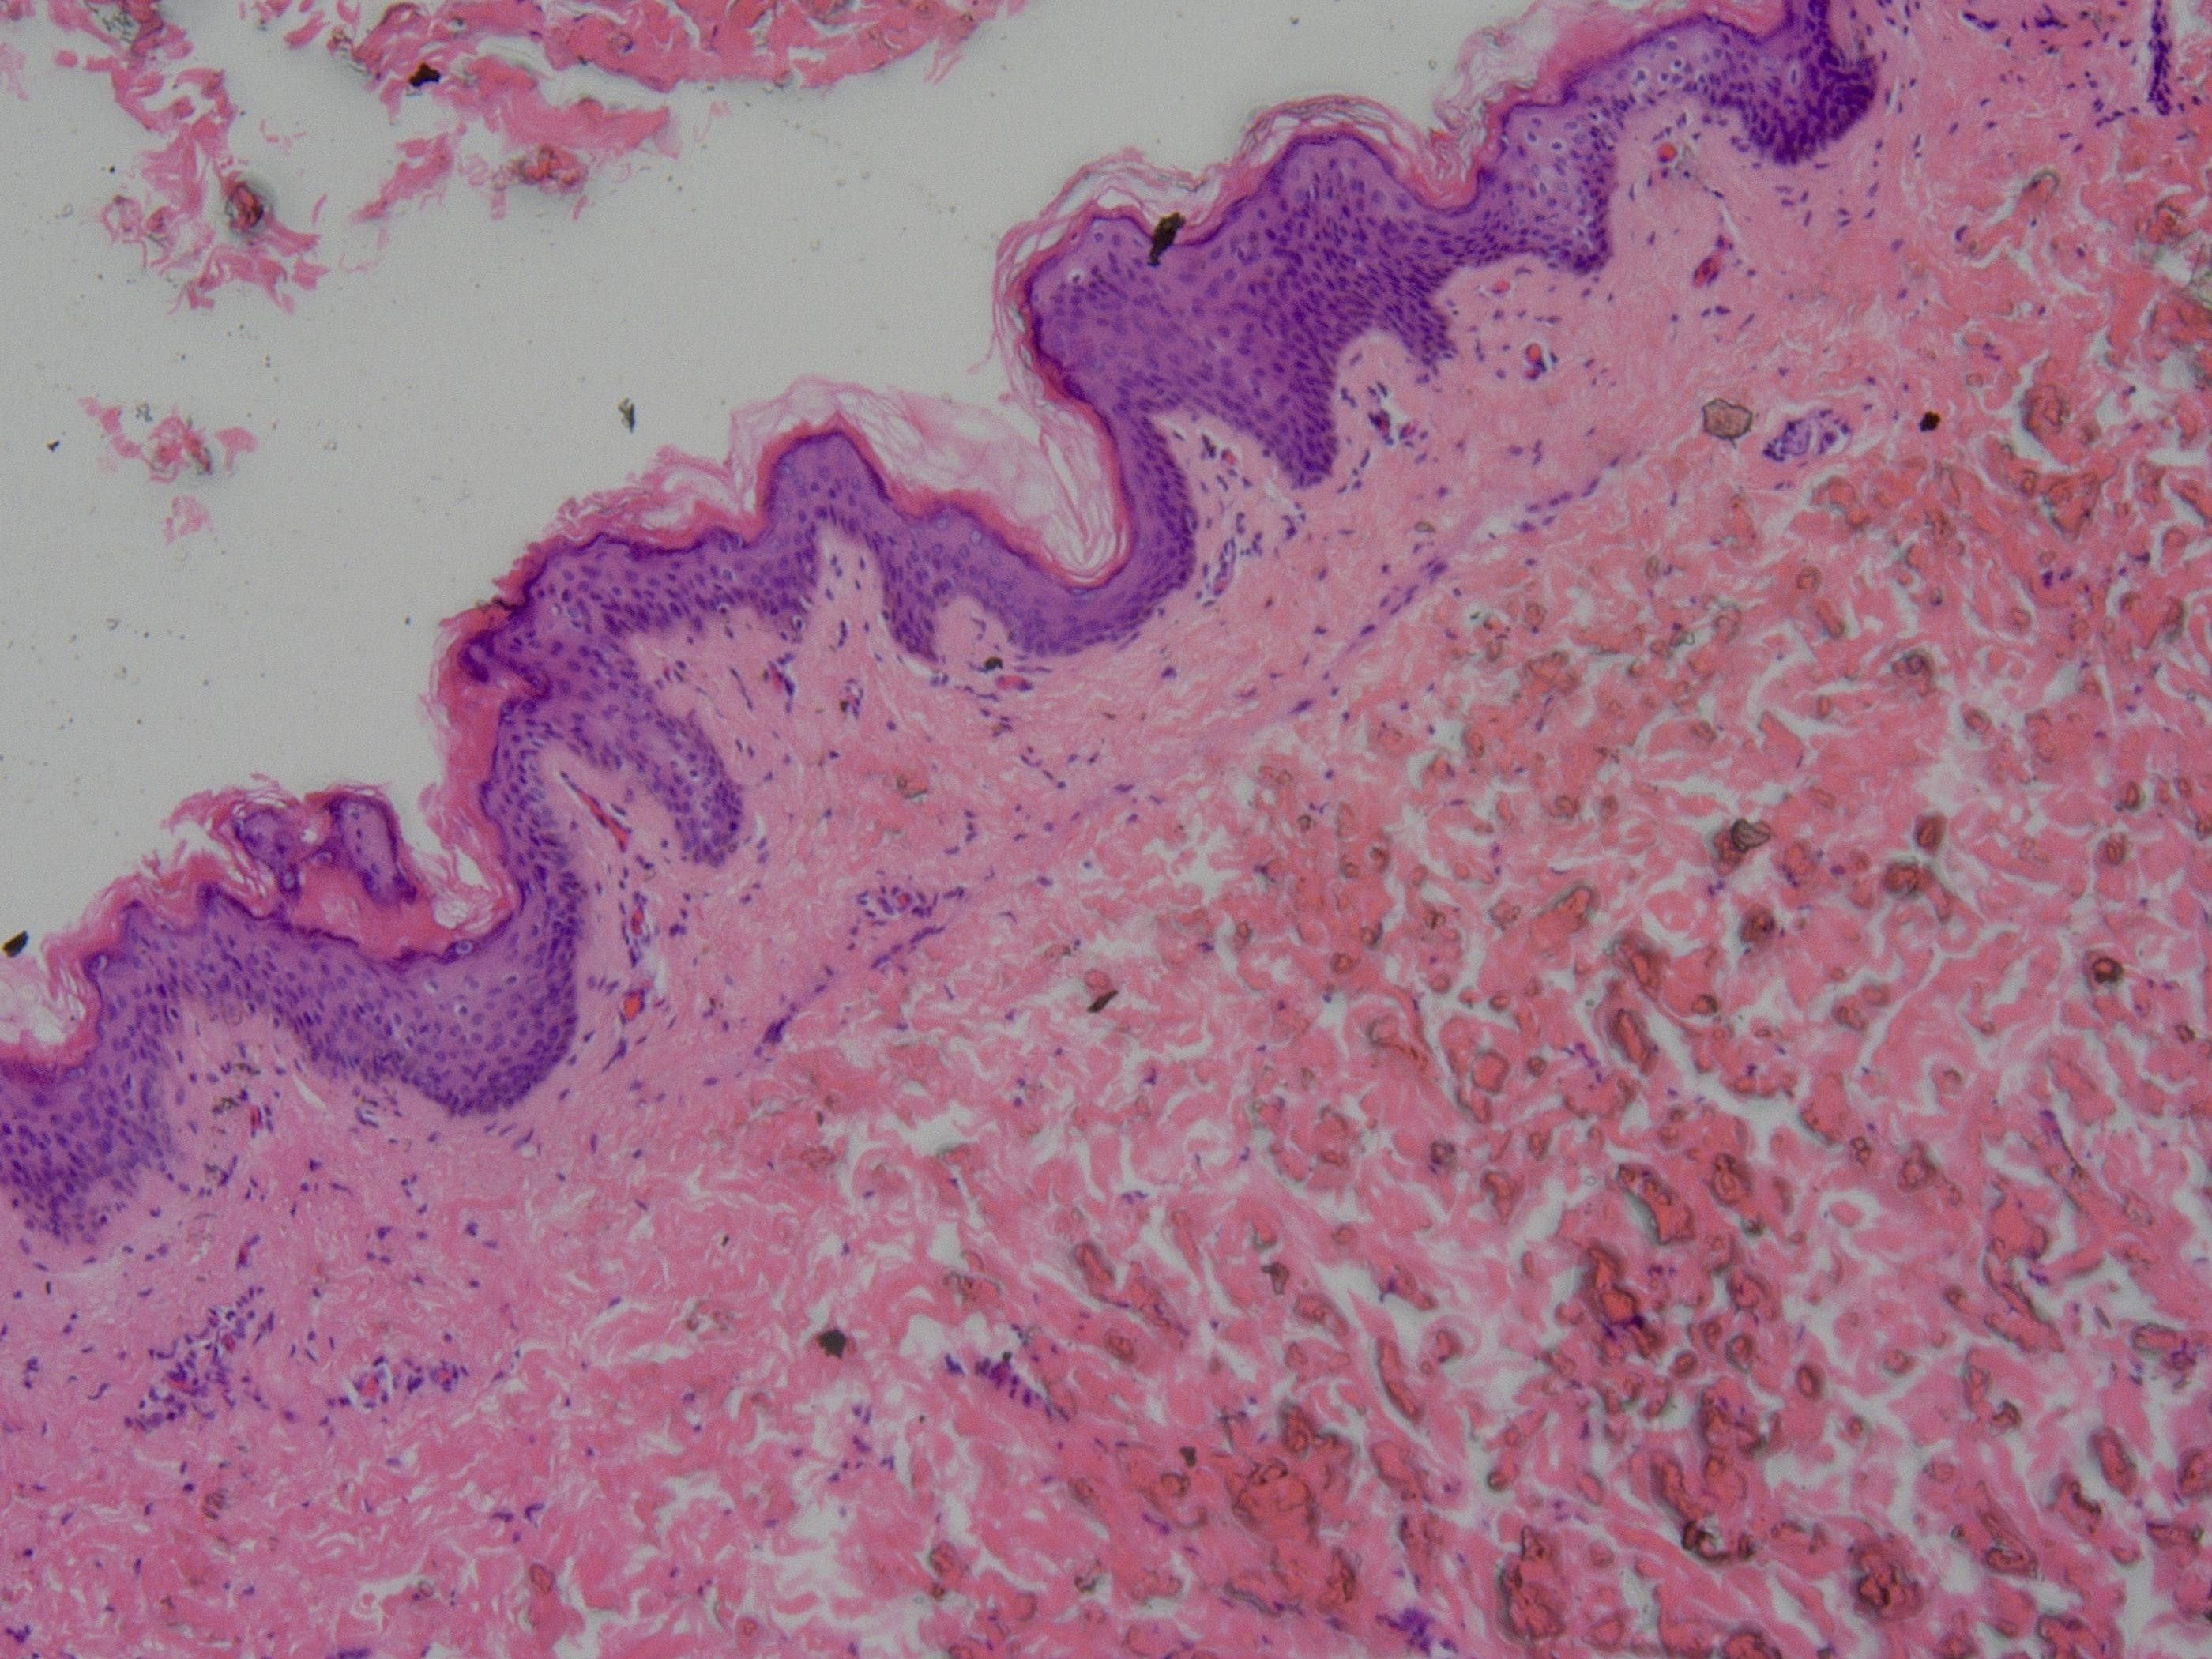

生物组织切片观察